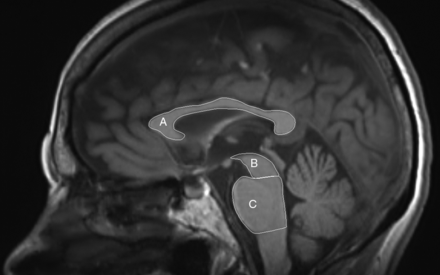

Midbrain, pons, and CC surfaces were measured at the midsagittal plane. Lines parallel to the mammillary–posterior commissural plane at the rostral and caudal pontine border were used to determine the midbrain and pons surfaces (Fig 1), according to the method of Kato et al.15 Middle cerebellar peduncle width was measured parasagittally, and superior cerebellar peduncle width was measured coronally (On-line Fig 1), according to the method of Longoni et al.16 The validity of the method has already been established as excellent, with low intra- and interrater variability of the measurements.16⇓–18 All surfaces were manually traced by G.V. with the DICOM viewer R3.0-Sp3 (Philips Healthcare, Best, the Netherlands).

MR imaging planimetry measurements. Midsagittal T1-weighted image depicts corpus callosum (A), midbrain tegmentum (B), and pons (C) surfaces.